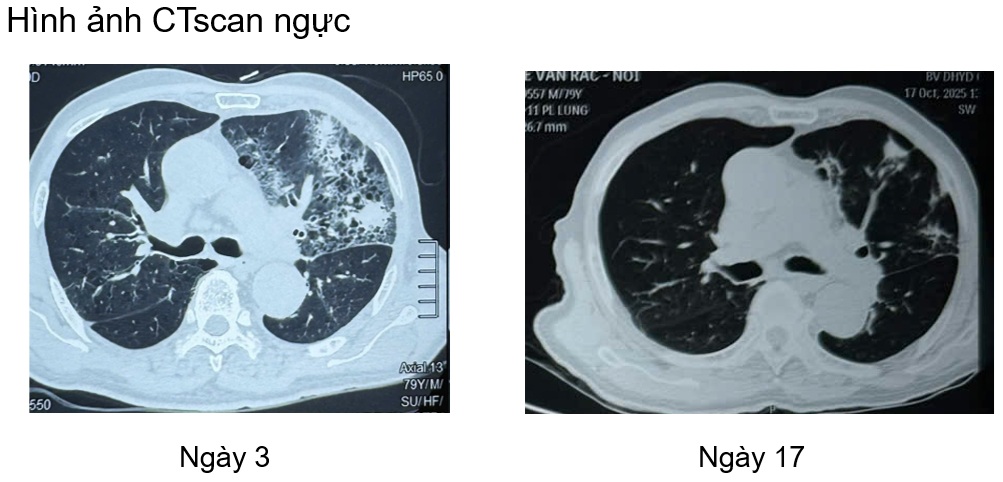

Một trường hợp lâm sàng tại khoa Nội tổng hợp, bệnh nhân nam L.V.R 80 tuổi, vào viện vì sốt, tiêu lỏng kèm khó thở, nặng ngực. Tiền sử tăng huyết áp, chưa ghi nhân bệnh lý hô hấp, bệnh mạn tính khác trước đó. Bệnh nhân nhập viện với tình trạng nhiễm trùng nhiễm độc, tổn thương thận cấp. Trong quá trình nằm viện bệnh nhân khó thở tăng dần suy hô hấp, sốt cao dao động 39 – 400C, đáp ứng kém với phác đồ kháng sinh ban đầu (piperacillin/tazobactam + levofloxacin). Bệnh nhân được nội soi phế quản, sau 5 ngày nhập viện kết quả cấy dịch rửa phế quản Candida albican, bệnh nhân được chỉ định phối hợp sử dụng kháng nấm anidulafungin. Sau 4 ngày sử dụng kháng nấm, lâm sàng bệnh nhân cải thiện hết sốt, ngưng được oxy, thở đều êm, chức năng thận hồi phục.

Bệnh nhân được tiếp tục duy trì phác đồ kháng nấm anidulafugin và fluconazole (hạ bậc kháng nấm), trong quá trình điều trị bệnh nhân được khám chuyên khoa mắt, theo dõi men gan, chức năng thận, bilan nhiễm trùng cũng như hình ảnh học (CTscan ngực, xquang ngực thẳng). Dưới đây một vài hình ảnh học trong quá trình điều trị nội, ngoại trú.